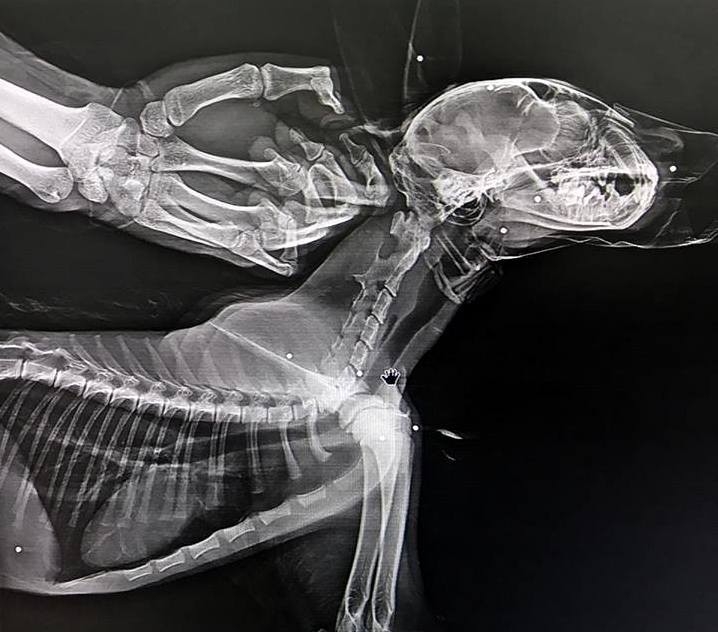

Genç ilçesi Soğuksu köyünde duyarlı vatandaşlar tarafından arazide fark edilen vaşak, Bingöl Doğa Koruma Milli Parklar Müdürlüğü aracılığıyla Kars Kafkas Üniversitesi Yaban Hayatı Kurtarma ve Rehabilitasyon Merkezine getirildi. Vücudunda saçmaların isabet ettiği belirlenen yaralı vaşak ameliyata alındı.

Vaşağın, Rehabilitasyon Merkezindeki muayenesinde çekilen röntgenlerde vücudunun çeşitli yerlerinde saçma taneleri bulunduğu tespit edildi. Gerekli tedavi ve rehabilitasyon işlemlerinin tamamlanmasının ardından vaşak, doğal ortamına bırakılacak.